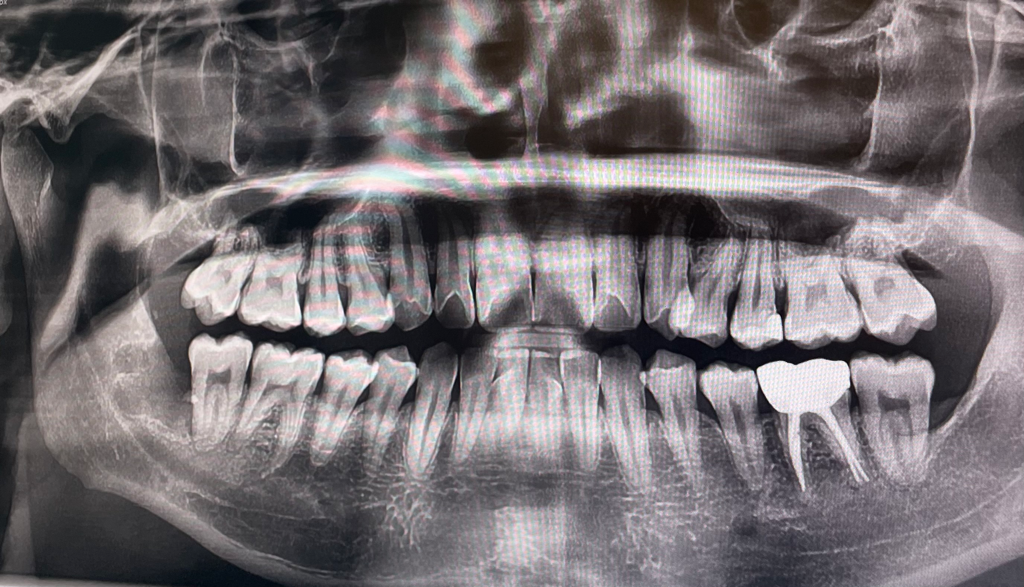

질기거나 딱딱한 음식을 먹을때 오른쪽 윗어금니 혹은 그 옆 치아 부분에 불편한 통증이 있습니다. 찌릿 하거나 저린 느낌의 통증은 아니고 묵직(?) 눌리는 느낌의 압통같은 통증이에요. 평상시나 일상적인 식사를 할때는 통증이 없고 뜨겁거나 차가운 음식이나 액체를 먹을때도 이렇다 할 통증은 없습니다.

위와같은 증상 관련해서 세군데의 치과를 가봤는데 모두 충치나 기타 특이사항은 없으니 지켜보자 말씀 하셨는데 여전히 질기거나 딱딱한 음식을 먹을때 편한 식사가 안 될 정도로 불편한 통증이 있습니다.. 선생님들 말씀으로는 한군데는 치아가 사선으로 자람으로 인해 씹는 과정에서 통증이 있을 수 있다 했고, 한군데는 엑스레이상 저 부분의 높이 차이로 교합시 통증이 생길 수 있으니 정 불편하면 어금니 부분 치아를 살짝 갈아내자 하셨습니다. 근데 여태 괜찮다가 갑자기 왜 이러는지 모르겠어요. 특이사항으로는 6월 8일에 오른쪽 아래 매복사랑니 발치를 했고 사랑니 발치 1주 전부터(사랑니 통증 때문) 발치 후 1주일 정도는 오른쪽으로 식사 하지 않았습니다.

아래 엑스레이 사진 첨부하겠습니다 ㅠㅠ

** 엑스레이상 어금니가 있는 사진은 올 초 겨울이고, 나머지 두장은 이번에 진료볼때 사진입니다.

사진상으로 보면 잇몸뼈가 많이 녹아 잇는것처럼 보입니다. 치아가 흔들린다면 그게 원인일수도 있습니다. 만약 흔들리지 않는데 치아가 불편하다면 치아에 금이갓을 가능성이 높습니다.